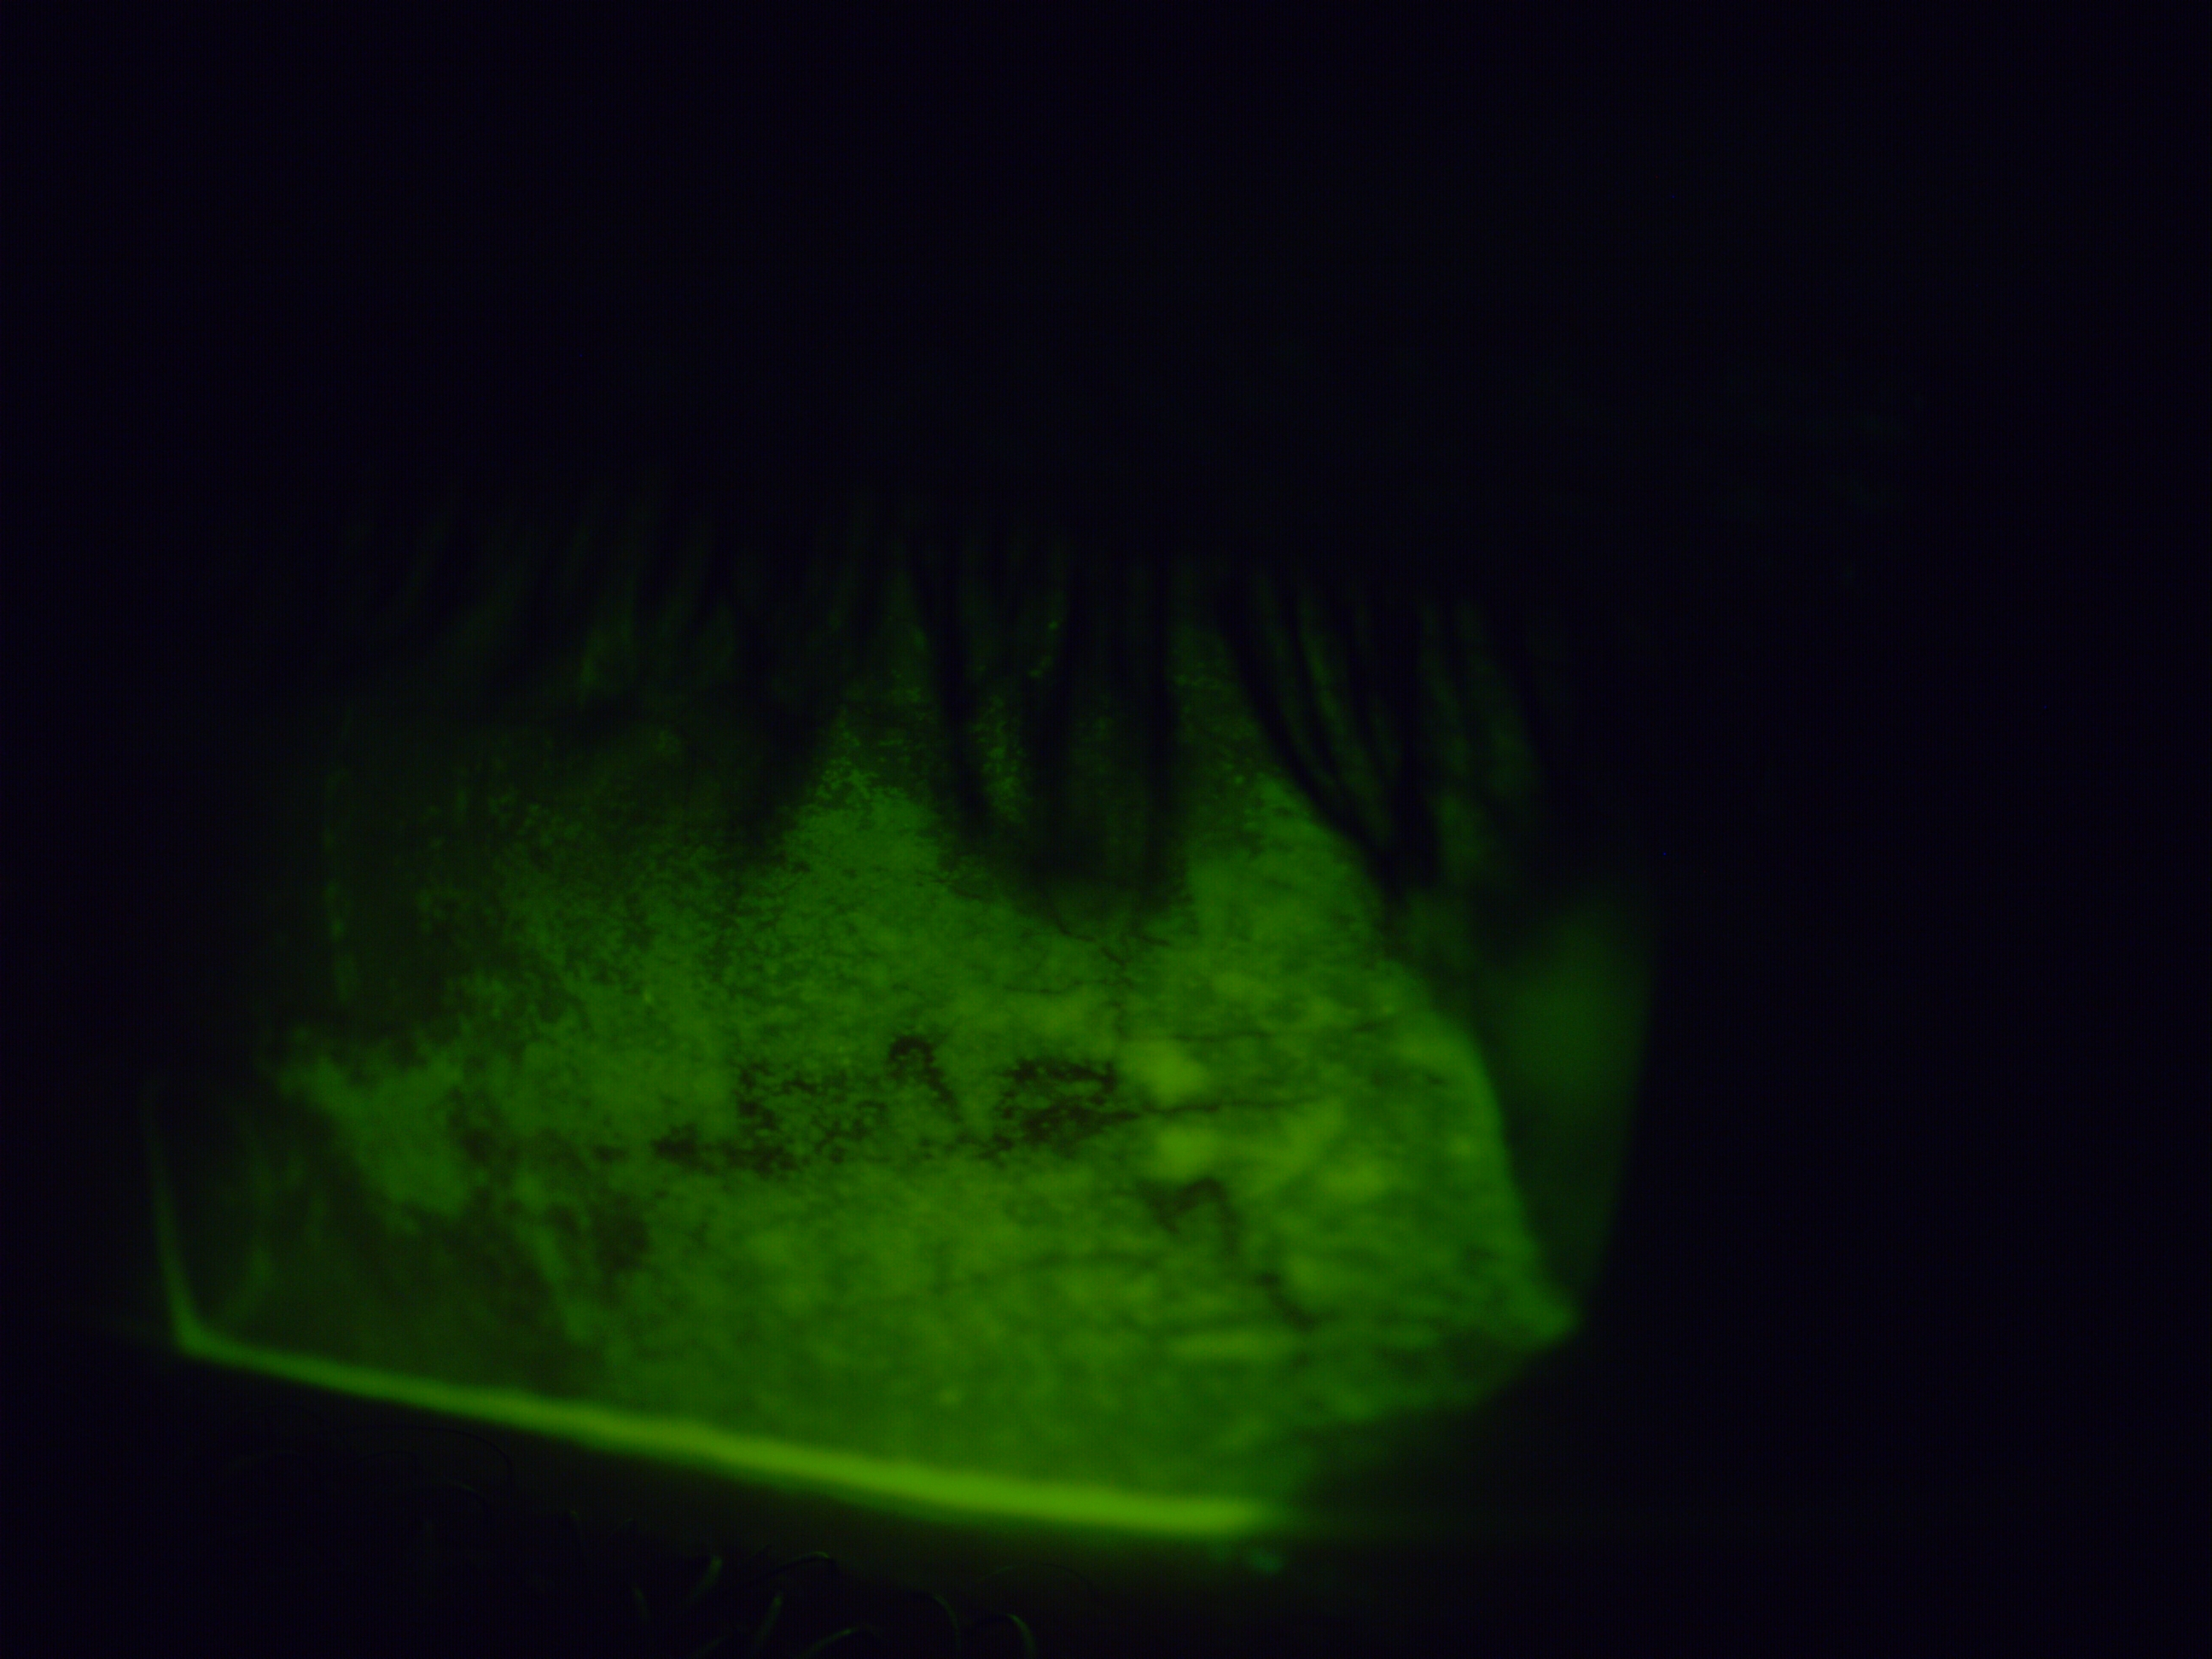

The images below were taken on presentation using fluorescein dye under cobalt blue light — damaged areas of the eye's surface absorb the dye and fluoresce brightly, showing the extent of the problem directly.

The improvement to the surface integrity is visible directly in the fluorescein image taken one week after removal — and reflected in the patient's symptoms. The chronic redness, the surface staining, and the subjective discomfort all showed meaningful improvement, with further gradual recovery continuing in the weeks that followed.